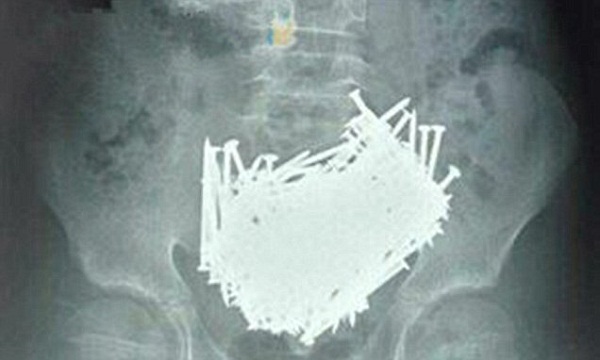

Old  Default Hơn 200 đinh nhọn trong bụng cậu bé 15 tuổi khiến bác sĩ kinh hãi

Một cậu bé người Trung Quốc đã khiến các bác sĩ phẫu thuật vô cùng kinh hãi khi tiến hành phẫu thuật vùng bụng. Không rõ vì lí do gì mà trong bụng cậu bé có hơn 200 cây đinh cùng nhiều vật nhọn khác.

Mới đây, một cậu bé 15 tuổi người Trung Quốc đã khiến các bác sỹ và gia đình bàng hoàng, sửng sốt khi phát hiện 200 cây đinh cùng các vật sắc nhọn khác trong ổ bụng.

Sau khi kiểm tra, các bác sỹ đã hết sức sửng sốt khi phát hiện dạ dày cậu bé chứa đầy đinh. Cậu bé ngay lập tức được đưa vào phòng phẫu thuật và lấy ra 200 cây đinh cùng những cây tăm, đá, đồng xu, tổng cộng những thứ đó nặng khoảng 680 gram.

Các bác sỹ thực hiện ca phẫu thuật cho biết họ chưa bao giờ gặp trường hợp nghiêm trọng như vậy. Cậu bé thú nhận rằng cậu ăn những dị vật đó qua đường miệng.

Cả bố và mẹ cậu bé đều ngỡ ngàng, không biết lý do tại sao con mình lại ăn những thứ kỳ quặc như thế. Có người cho rằng cậu bé có thể đã mắc bệnh Pica, một chứng rối loạn ăn uống khiến cho người bệnh thèm ăn bất cứ thứ gì như đất đá, thủy tinh, các đồ kim loại…